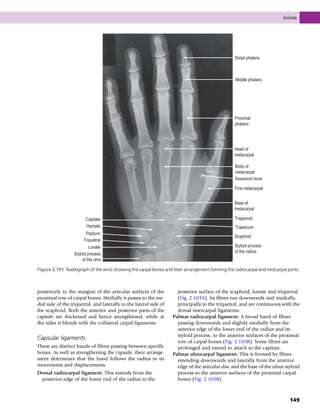

• 225.

sciatic notch; inferiorlyit ends as the blunt medially pro- jecting ischial spine, below which is the groove forming the lesser sciatic notch. The pelvic surface of the body is con- tinuous with the pelvic surface of the ilium, forming part of the lateral wall of the pelvis. Acetabulum The acetabulum is formed by the fusion of the three com- ponents of the innominate; the ilium, ischium and pubis meet at a Y-shaped cartilage which forms their epiphyseal junction. The anterior one-fifth is formed by the pubis, the posterosuperior two-fifths by the body of the ilium, and the posteroinferior two-fifths by the body of the is- chium. It is a hemispherical hollow on the outer surface of the innominate, facing downwards, forwards and later- ally. The prominent rim of the acetabulum is deficient in- feriorly, forming the acetabular notch. The rim gives attachment to the acetabular labrum of the hip joint; its uneven internal edge provides an attachment for the synovial membrane of the joint. The acetabular labrum continues across the acetabular notch to produce the trans- verse ligament. The transverse ligament and margins of the notch give attachment to the ligament of the head of the femur. The heavy wall of the acetabulum consists of a semi- lunar articular portion covered with hyaline cartilage, open below, and a deep, central non-articular portion, the ace- tabular fossa. The acetabular fossa is formed mainly from the ischium, and its wall is frequently thin. Obturator foramen A large aperture ringed by the sharp margins of the pubis and ischium, those of the pubis overlapping each other in a spiral forming the obturator groove, which runs obliquely forwards and downwards from the pelvis into the thigh, being converted into a canal by a specialization of the obturator fascia. The obturator membrane is at- tached to the margins of the foramen, except superiorly at the obturator groove. Iliac fossa Anterior superior iliac spine Anterior inferior iliac spine Arcuate line IIiopubic eminence Pubis Obturator foramen Ischial tuberosity Lesser sciatic notch Ischial spine Greater sciatic notch Posterior inferior iliac spine Posterior superior iliac spine Iliac tuberosity Iliac crest Auricular surface Figure 3.8 Left innominate, medial view. Part | 3 | The lower limb 210

• 226.

Ossification Each innominate boneossifies from eight centres – three primary centres, one each for the ilium, ischium and pubis; and five secondary centres, one each for the iliac crest, the anterior inferior iliac spine, the ischial tuberosity, the pubic symphysis and the triradiate cartilage at the centre of the acetabulum. The sequence of ossification has functional significance because of the support given to the pelvic or- gans and its role in weight transmission. The primary ossi- fication centres appear during the third, fourth and fifth months of development in the ilium, ischium and pubis re- spectively. At birth the ilium, ischium and pubis are quite separate and the secondary ossification centres have not yet appeared. By the age of 13 or 14 years, the major parts of the ilium, ischium and pubis are completely bony but are still separated by the Y-shaped triradiate cartilage in the acetabulum. At the age of 8 or 9 years, three major cen- tres of ossification appear in the acetabular cartilage. The largest appears in the anterior wall of the acetabulum and fuses with the pubis. Further centres appear in the iliac acetabular cartilage superiorly, which fuses with the ilium, and in the ischial acetabular cartilage posteriorly, which fuses with the ischium. Fusion of the three bones in the ac- etabulum occurs between 16 and 18 years. The other sec- ondary ossification centres appear at about puberty and unite with the major bones between 20 and 22 years. Palpation The anterior superior iliac spines can easily be palpated in the living, particularly in females where they tend to be fur- ther apart. They are situated at the anterior end of the iliac crest, being found in the upper part of the pocket area. Trac- ing backwards from these spines, the iliac crest is easily pal- pable, having a large tuberosity about 5 cm from its anterior end. Following the crest as far back as possible, the smaller posterior superior iliac spines can be felt. These are situated in dimples in females, while in males each ap- pears as a small raised tubercle. About 10 cm below the centre of the iliac crest, the greater trochanter of the femur can be clearly felt. In sitting, the body rests on the ischial tuberosity of each innominate bone; if the hands are placed under this area the tuberosities can be easily felt. This part of the tuberosity is covered with a bursa which often becomes painful and swollen when sit- ting for too long on a hard surface; this is termed a bursitis. If the hands are drawn down the front of the abdominal wall, about 5 cm above the genitalia, a bony ring can be felt. This has a central depression where the pubic symphy- sis is situated with each pubic tubercle about 1 cm above and lateral on either side. The sacrum A triangular bone with the apex inferior, it consists of five fused vertebrae broadened by the incorporation of large costal elements and transverse processes into heavy lateral masses, which lie lateral to the transverse tubercles on the back of the sacrum extending between the anterior sacral fo- ramina onto the front of the bone; the auricular surface lies entirely on the lateral mass. It is wedged between the poste- rior parts of the two innominates with which it articulates at the sacroiliac joints. The pelvic (anterior) surface (Fig. 3.9A) is concave and relatively smooth, being marked by four transverse ridges separating the original bodies of the five sa- cral vertebrae. Lateral to each ridge is the anterior sacral fo- ramen, representing the anterior part of the intervertebral foramen; the foramina are directed laterally and anteriorly. The dorsal surface (Fig. 3.9B) is convex and highly irreg- ular with posterior sacral foramina, medial to which the ver- tebral canal is closed over by the fused laminae. However, the spinous processes and laminae of the fourth and fifth sacral vertebrae are usually absent, leaving the vertebral ca- nal open. This is the sacral hiatus, an inferior entrance to the vertebral canal, which may be used, for example during la- bour, to introduce an anaesthetic agent to block the sacral nerves. Posteriorly, in the midline, the reduced spinous processes form the median sacral crest. Lateral to the poste- rior sacral foramina are the prominent lateral sacral crests, representing the transverse processes, which provide at- tachment for the dorsal sacroiliac ligaments, and inferiorly for the sacrotuberous and sacrospinous ligaments. Medial to the posterior sacral foramina are the indistinct intermedi- ate sacral crests, representing the fused articular processes. The superior articular processes of the first sacral vertebra are large and oval, being supported by short heavy pedicles. Their facets, for articulation with the inferior articular sur- faces of the fifth lumbar vertebra, are concave from side to side and face posteromedially. The tubercles of the inferior articular processes of the fifth sacral vertebra form the sacral cornua and are connected to the cornua of the coccyx. The lateral surface (Fig. 3.10A) is triangular, being nar- rower below. The upper part is divided into an anterior smoother pitted auricular surface, covered in cartilage, for articulation with a similar area on the ilium. The rougher posterior area has three deep impressions for attachment of the powerful posterior sacroiliac ligaments. The superior surface (Fig. 3.10B) faces anterosuperiorly and has a central oval area which is the upper surface of the first sacral verte- bra; it is separated from the fifth lumbar vertebra by a thick intervertebral disc. Its anterior projecting border is the sa- cral promontory. On each side of the body of the sacrum is the ala, formed by the fusion of the costal and transverse processes of the first sacral vertebra. When articulated with the innominate, the ala of the sacrum is continuous with the ala of the ilium. Ossification Primary centres appear in the sacrum between the third and eighth month in utero; one for each vertebral body, one for each half of each vertebral arch, and one for each costal Bones 211

• 227.